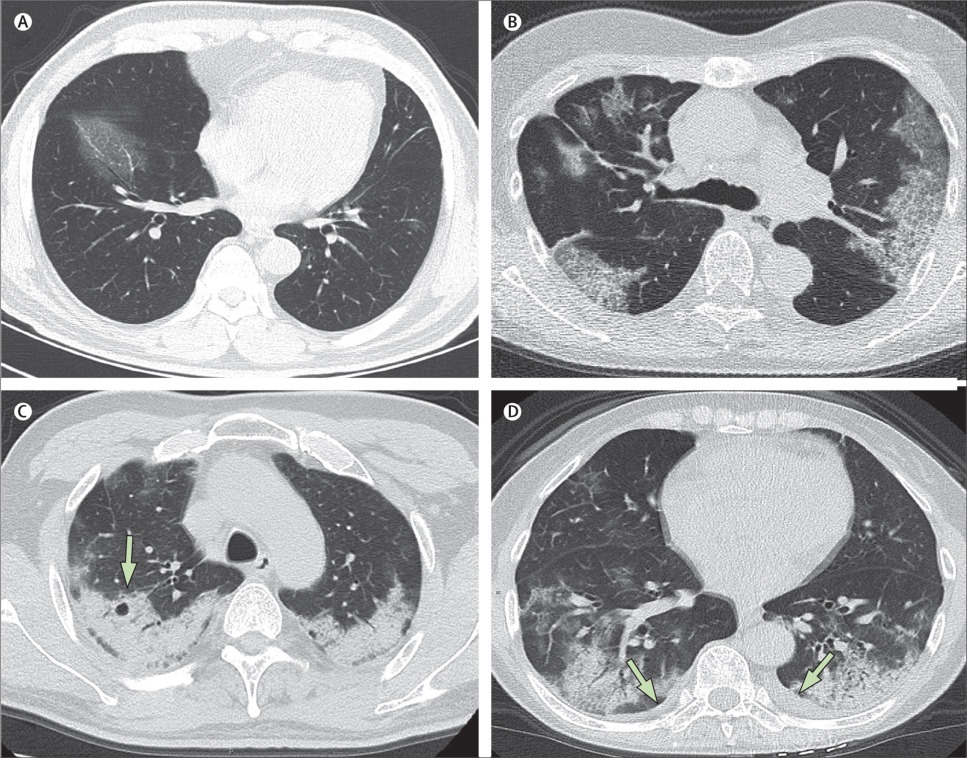

Hình CT chụp phổi của các bệnh nhân -19 tại Trung Quốc.Hình A: Bệnh nhân nam 56 tuổi, ngày thứ 3 sau khi khởi phát triệu chứng, phổi xuất hiện các đốm trắng từ vách liên sườn đến nội nhãn ở thùy dưới bên phải. Hình B: Bệnh nhân nữ 74 tuổi, ngày thứ 10 sau khi khởi phát triệu chứng: hai bên phổi dày đặc những đốm trắng chứng tỏ sự xâm chiếm và phá hủy nặng của virus tới các phế nang. Hình C: Nữ bệnh nhân 61 tuổi, ngày 20 sau khi khởi phát triệu chứng: phổi bị bao phủ bởi lớp trắng mờ đục dày, các phế nang bên trong đã bắt đầu biến đổi. Hình D: Nữ bệnh nhân 63 tuổi, ngày 17 sau khi khởi phát triệu chứng: hai bên phổi xuất hiện lớp đốm trắng dày trong phế quản ở cả thùy dưới lẫn thùy trên, đã có hiện tượng tràn dịch màng phổi. Ảnh: The Lancet.